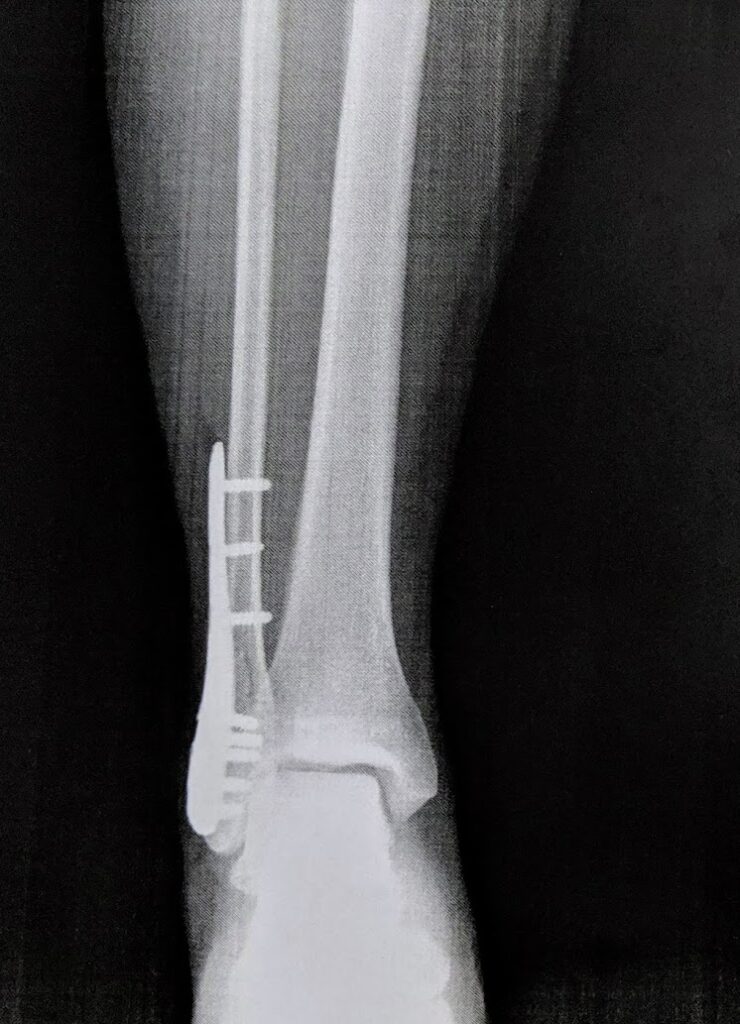

折れたところにプレートをねじで止めているので、そりゃ痛いですよね。

プレートは1年以内に取る予定だった

プレートを入れた後、このプレートは、1年以内に取っていいそうです。

そのため今でもプレートは右足に入っています。